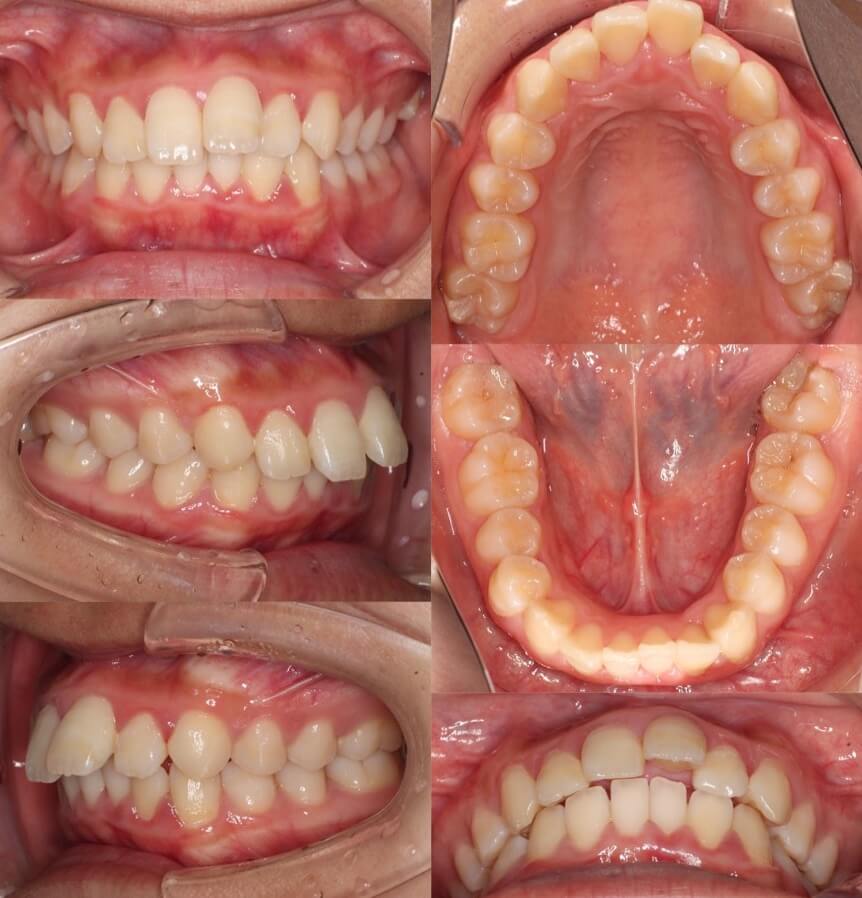

高校生男子・マウスピース型矯正装置・抜歯

<顔のビフォーアフター>

<症例概要>

主訴:出っ歯

年齢・性別:16歳男子(高校生)

住まい:千葉県八千代市

症状:上顎前突・下顎後退

治療方針:抜歯空隙の閉鎖(中等度固定)

治療装置:マウスピース型矯正装置(アライナー装置)

抜歯:上左右第一小臼歯(計2本)

治療期間:2年(1週間交換)

アライナー枚数:52+19+16ステージ

リテーナー:上下プレートタイプ+クリアタイプ

治療費用:990,000(税込)

代表的副作用:痛み・治療後の後戻り・歯根吸収・歯髄壊死・歯肉退縮

▶︎その他の副作用

【治療シミュレーション】

上の抜歯スペースにゆっくりと前歯を後ろに引き込みむ計画です。II級ゴムをかけてもらいます。

※マウスピース型カスタムメイド矯正歯科装置は完成物薬機法対象外の矯正装置であり、医薬品副作用被害救済制度の対象とはならない可能性があります。

上下の前歯の隙間12mmある著しい出っ歯で症例です。上の第一小臼歯を抜歯し上の前歯を8mm引っ込めた症例です。高校生であったので下顎の成長もあり上手く口元の突出感もなくなりました。上の歯列は治療途中で生えてきた親知らずも並べています。